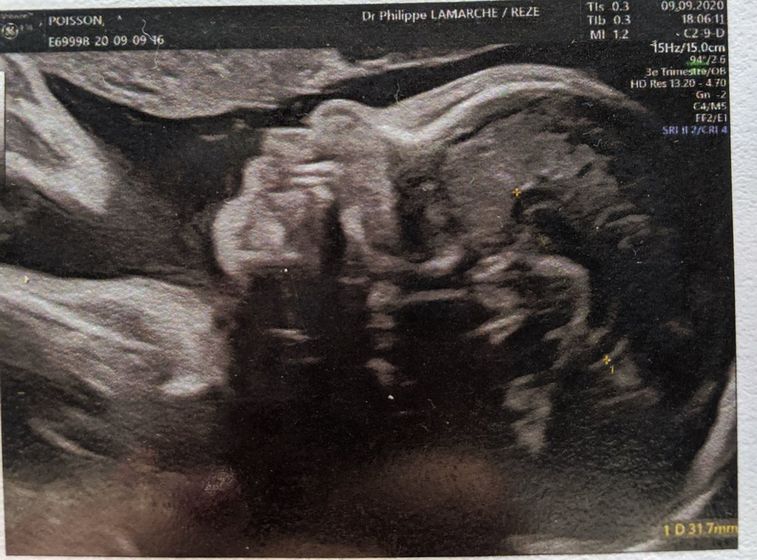

У меня по ходу будут близняшки с разницей 2 года ? на первом фото первый сын на 2м сегодняшняя фотка с экографии (26 недель), на 3 сын через несколько дней после рождения и на последнем сегодняшнее 3Д. Буду ждать 3 скрининга чтобы опять увидеть второго сыночка. Ребёнок весит 842гр в 26 недель, сказали что родится скорее всего нормального размера даже при боковом прикреплении плаценты.Даниэль родился 4кг и думаю этот будет 3700/3800 ?. Сколько ваши малыши весили примерно в 26 недель? *к стати на первом фото Даниэль сосёт палец по этому губа чуть чуть плоская.

Вообще похожи сильно

Действительно похожи!!!

☺️ Похожи